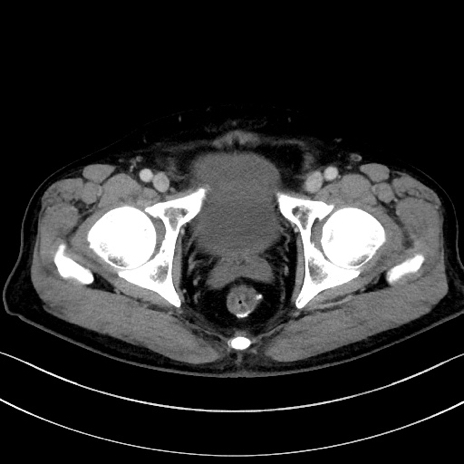

症例15(横断像)

【症例】70歳代男性

【主訴】腹痛

【現病歴】今朝から腹痛あり。全体的に痛い。特に左上の方。排ガスが今日はない。冷や汗が出る。

【既往歴】直腸癌術後

【身体所見】左側腹部〜上腹部に圧痛あり。腹膜刺激症状明らかなではない。軽度反跳痛。左下腹部に術後瘢痕あり。

【データ】WBC 7700、CRP 0.02